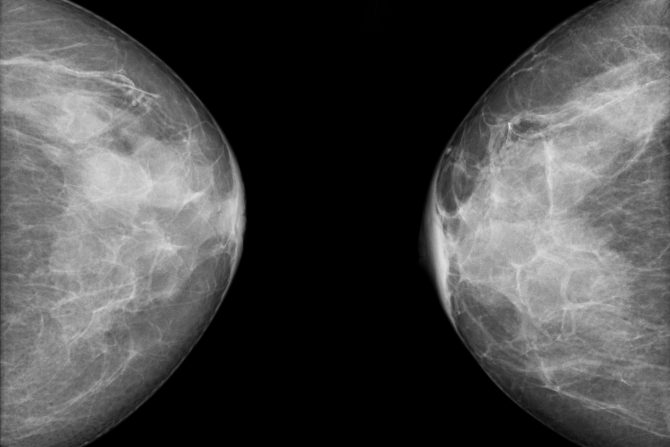

Da li žena ima guste grudi ili ne određuje se mamografskim pregledom koji pokazuje gustinu tkiva dojki i to stanje samo mamograf može da pokaže. Grudi sadrže žlezdano, vezivno i masno tkivo. Gustina dojki ili mamografska gustina je termin koji se koristi da opiše različite proporcije ovih tipova tkiva koje detektuje mamograf.

Kako izgledaju guste grudi?

Gušće grudi imaju relativno velike količine vezivnog i/ili žlezdanog tkiva a manje masnog tkiva. Gustina grudi nema nikakve veze sa izgledom, osećajem, veličinom ili čvrstoćom, a smatra se da žene sa gustim grudima imaju veći rizik od dobijanja raka dojke.

Na mamografu, vezivno ili vlaknasto tkivo izgleda belo, dok je masno tkivo tamno. S obzirom na to da se rak dojke prikazuje kao bela tačka/masa to može da oteža specijalistima da identifikuju karcinom kod žena sa gustim grudima. Međutim, čak i sa gustim grudima, skrining mamograf je i dalje najefikasniji metod za rano otkrivanje raka dojke za žene starije od 50 godina. Guste grudi su takođe češće kod mlađih žena ili žena sa nižim indeksom telesne mase. Pored toga, gustina grudi se smanjuje kako žene postaju starije.

Gustina grudi odražava količinu vlaknastog i žlezdanog tkiva u ženskim dojkama u poređenju sa količinom masnog tkiva u dojkama, kao što se vidi na mamografu. Mamografski izveštaj razlikuje 4 kategorije gustih grudi:

• Grudi su skoro u potpunosti masne i takve grudi ima oko 10 odsto žena

• Nekoliko područja gustog tkiva rasuto je kroz grudi i to je slučaj kod oko 40 procenata žena

• Grudi su svuda ravnomerno guste i to je stanje kod oko 40 odsto žena. Ova vrsta tkiva se u mamografskom izveštaju naziva i „heterogeno gusto“ tkivo

• Grudi su izuzetno guste, i takve su kod oko 10 procenata žena.

Za žene u prve dve kategorije kaže se da imaju neguste ili masne grudi, dok žene u druge dve spadaju u kategoriju onih sa gustim grudima. Statistika pokazuje da oko polovina žena starijih od 40 godina ima guste grudi.